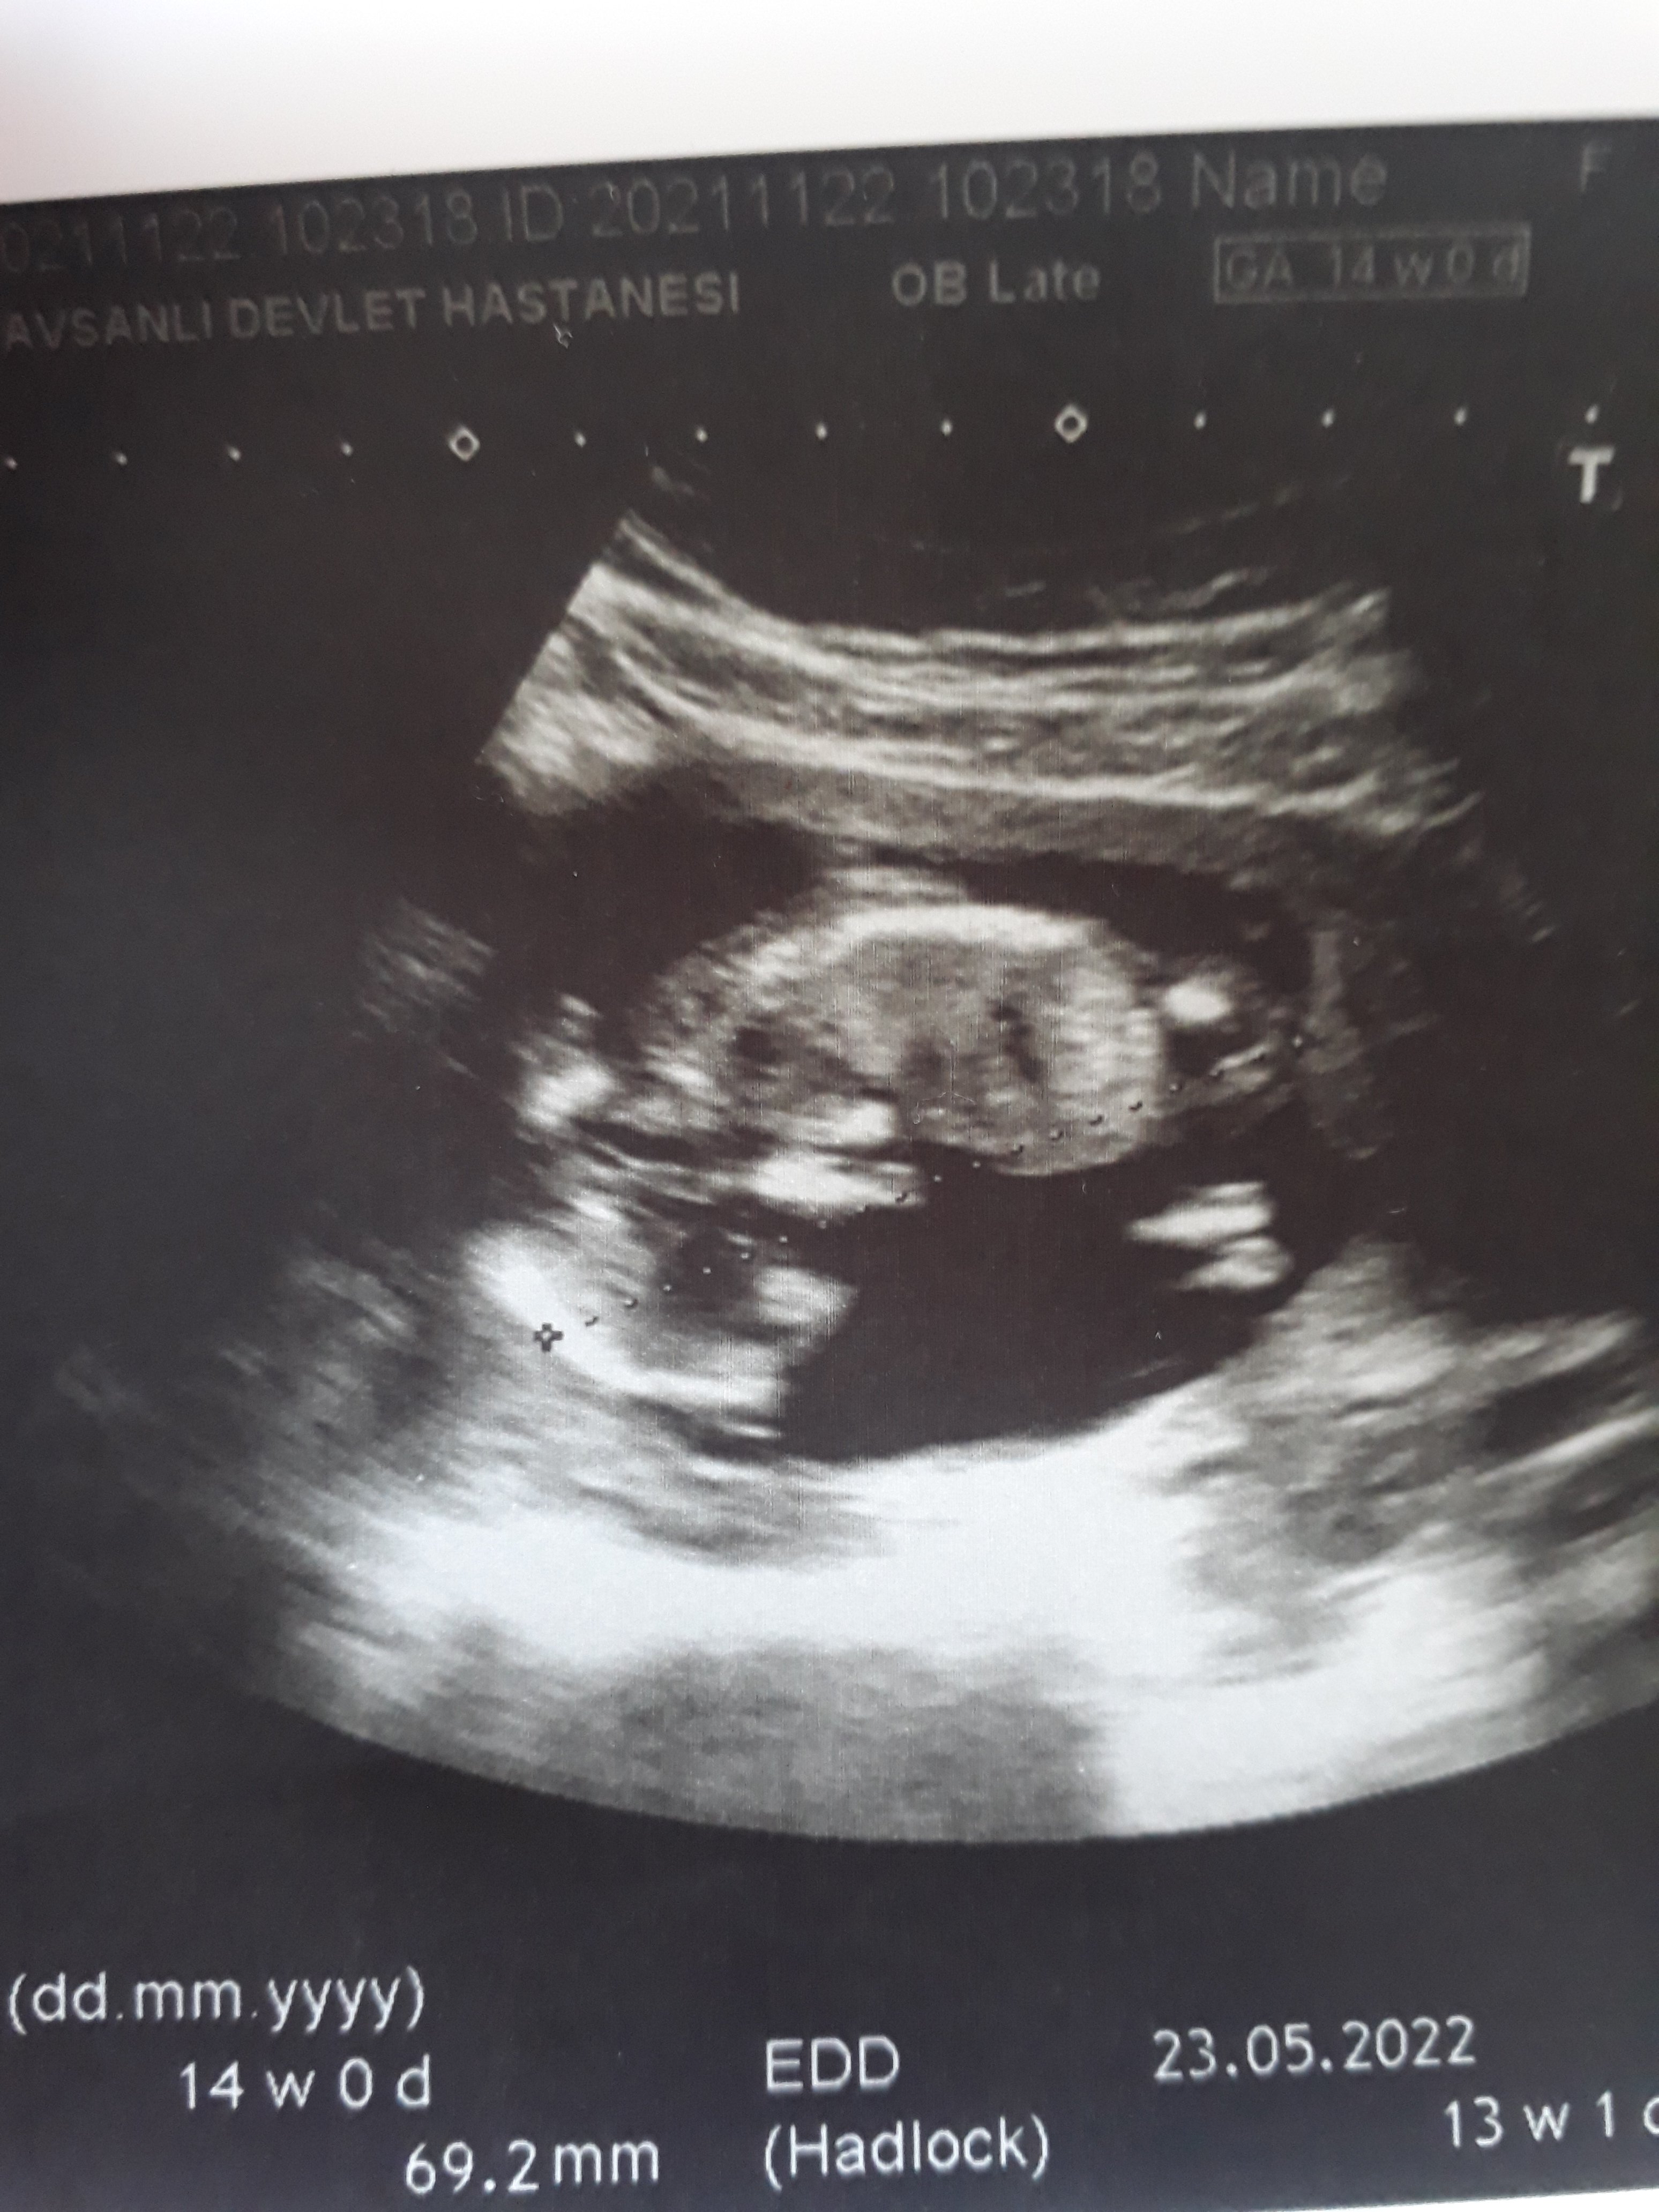

Resme bakarmisniz😊😊cinsiyeti soylemedi doktor

Ins canim banada kiz gibi gelio ya bilmiom dojtora sordum kabarıklık gordum dedi şeyinde😂bende sustum bisiy demedim sonra doktor 15gine daha belli olur dedi 🙃